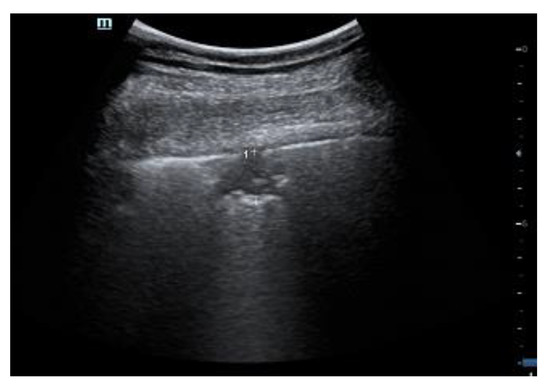

2.1. Characteristics of the Pleural Line

| 1 | Pleural line has slight alterations with sporadic vertical bright artifacts. The presence of relatively small acoustic channels due to focal interstitial thickening is speculated. |

| 2 | Pleural line has relevant alterations. Progression of subversion of peripheral air space geometry causes a predominance of vertical artifacts. Small subpleural consolidations, related to deaeration, can be present. |